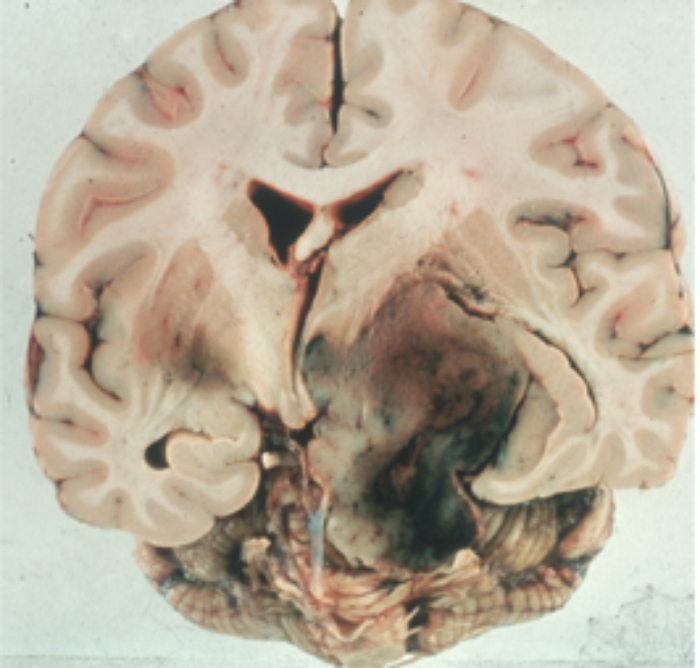

Figure 4: Pathological specimen of a large pituitary tumour extending laterally into

the temporal and parietal lobes of the brain with intra tumour haemorrhage.

If untreated a pituitary tumour will continue to expand slowly over months or years, most commonly upwards (Figure 3, left) causing further compression of the visual pathway and eventually blindness. Lateral spread is into the cavernous sinus (Figure 3, right) when an ocularmotor palsy, usually the sixth, will develop. Once the cavernous sinus is invaded, a tumour in this area cannot be safely removed. Rarely a tumour can extend even further into the temporal or parietal lobe of the brain (Figure 4).